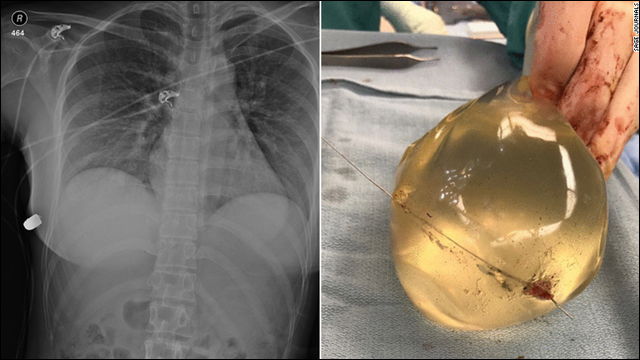

韓国大手美容クリニックにてプロテーゼを挿入したが、2年半経過したころ、鼻の先端に発赤が認められて、受診した。すると、鼻の内部にプロテーゼが露出しているのが見つかり、即座に摘出術を行った。(略)